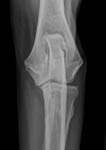

Gesundheitsstatus vom 26.11.2018 Die Röntgenbilder zeigen keinen Hinweis auf HD oder ED bei Lena vom Gehrensee. Die veterinärmedizinischen Untersuchungen von Jana auf HD, ED u. DCM und die Zuchtzulassungsprüfung wurden erfolgreich bestanden.

Die Gelenke sind HD und ED - frei, das Herz ohne Befund. Vor dem Hintergrund, dass seit 5 Generationen alle Zuchthündinnen bis ins hohe